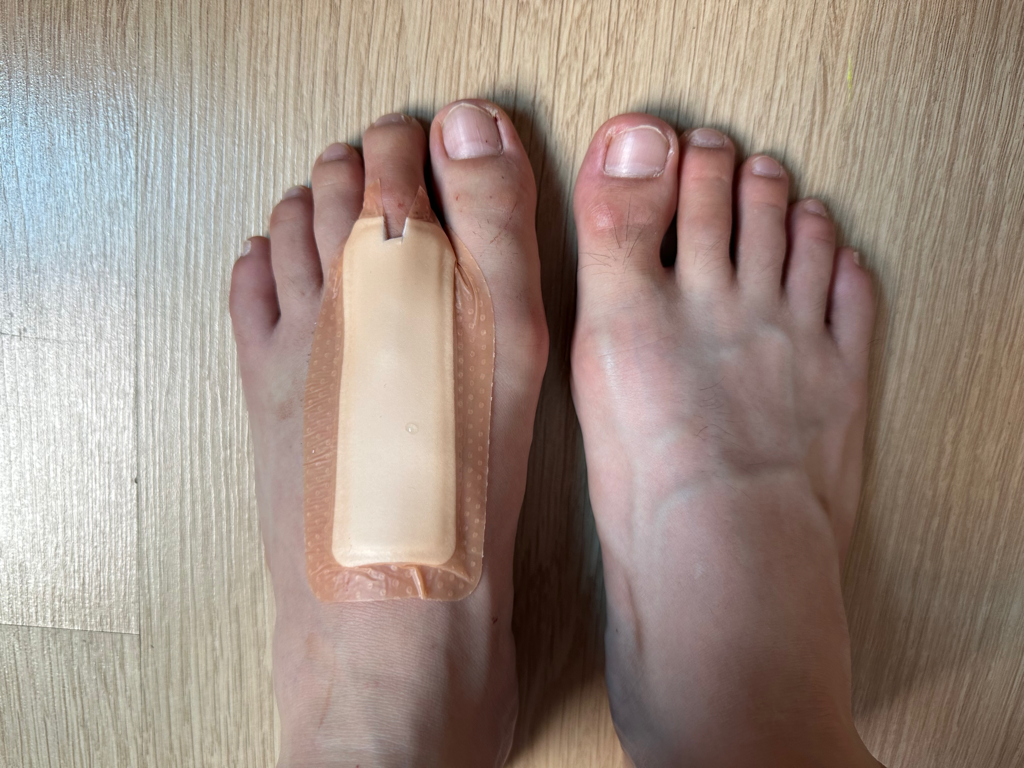

붓기와 부어서 색깔이 변한 범위가 점점 커지는 것 같아요. 보라색에 가까워지는?

22일 오전 11시

23일 오전 8시

23일 오후 8시

24일 오전 10시

핀제거 전